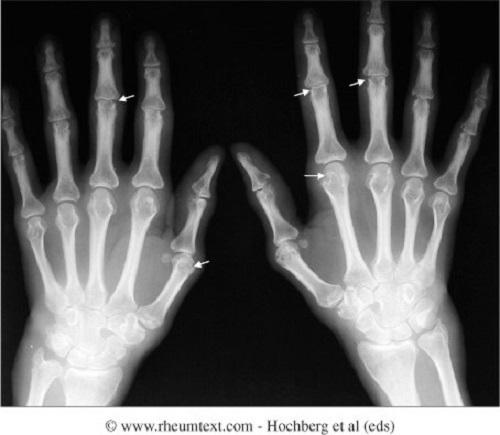

Ποιά όμως είναι η φύση της νόσου; Η ουρική αρθρίτιδα οφείλεται σε μια διαταραχή του μεταβολισμού του ουρικού οξέος. Αυτό καθιζάνει στους αρθρικούς ιστούς [αλλά και αλλού π.χ. ουροποιητικό] και δημιουργεί φλεγμονή με αποτέλεσμα πόνο, δυσκινησία και αρθρική καταστροφή. Η υπερουριχαιμία [αύξηση του ουρικού οξέος στο αίμα] οφείλεται α] σε αυξημένη παραγωγή του [10%] από διάφορα αίτια [άγνωστα, διαταραχές ενζύμων αυξημένη πρόσληψη από τις τροφές, έντονος καταβολισμός νεοπλασίες, ψωρίαση αιμολυτική αναιμία,αλκοολισμός] και β] σε μειωμένη απέκριση του στους νεφρούς απο κακή νεφρική λειτουργεία, αφυδάτωση, σε νόσους όπως η υπέρταση, από φάρμακα όπως τα διουρητικά και τέλος από άγνωστα αίτια. Η ουρική δεν είναι μία νόσος αλλά έχει πολλές μορφές όπως 1] Η οξεία κρίση 2]Η υποξεία διαλείπουσα αρθρίτιδα με μεσοδιαστήματα ηρεμίας και 3] Η χρονία τοφώδης αρθρίτιδα που οφείλεται στην συσώρευση ουρικού οξέος στους ιστούς [ουρικοί τόφοι] Η ουρική αρθρίτιδα δε βλάπτει μόνον τις αρθρώσεις και τα περιαρθρικά μόρια όπως ορογόνους θυλάκους και τένοντες αλλά και άλλα όργανα όπως τα νεφρά, τις ουροφόρες οδούς [π.χ. ουρολιθίαση] Η διάγνωση της ουρικής αρθρίτιδας δεν είναι μια ¨απλή υπόθεση¨ και δεν εξαντλείται στη φυσιολογική ή μη εργαστηριακή τιμή του ουρικού οξέος στο αίμα. Τιμές κάτω από αυτήν μπορεί να προκαλέσουν κρίση και αντιστοίχα ψηλότερες τιμές δεν δημιουργούν πάντα συμπτώματα. Ο γιατρός συνεκτιμά πολλούς παράγοντες όπως κλινική εικόνα, τρόπος ζωής, κληρονομικότητα και συνυπάρχουσες παθήσεις. Μπορεί να παραγγείλει εξείδικευμένες εξετάσεις όπως μικροσκοπική εξέταση αρθρικού υγρού,ακτινογραφίες, μέτρηση ουρικού οξεος στα ούρα για να καταλήξει σε ασφαλή διάγνωση.